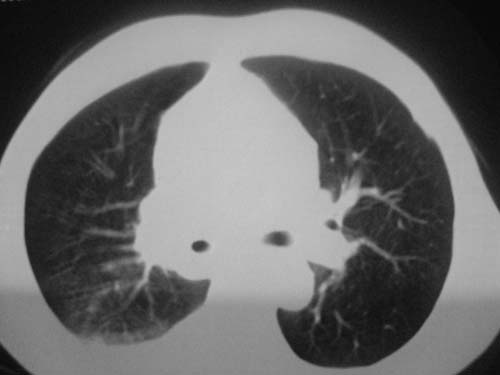

以下是引用科室第一人在2010-3-25 20:30:00的发言:[br]1:纵膈肿瘤性病变,恶性胸腺瘤可能性大伴纵膈右肺门淋巴结转移,右侧胸腔积液。[br]2:右侧肺门肿瘤性病变,纵膈淋巴结转移,右侧胸腔积液。右下叶转移。

以下是引用子期在2010-3-25 21:00:00的发言:[br]先考虑右中央型肺癌伴转移。

以下是引用江广1996在2010-3-25 22:49:00的发言:[br]通常肺癌向纵隔转移多见,纵隔肿瘤向肺内转移少见(有的表现为向肺内侵润)。本例以一元论考虑:右中心型肺癌并纵隔淋巴等多处转移。[br][br][本贴已被 江广1996 于 2010-3-25 22:50:07 修改过]

以下是引用yangyudong333在2010-3-26 6:43:00的发言:[br]“冰冻纵膈”,考虑纵膈淋巴瘤伴肺内及胸膜侵润。